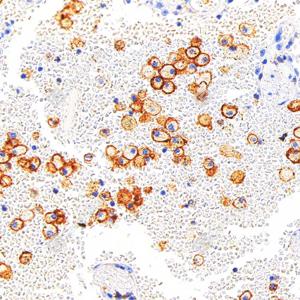

IHC检测CD11c蛋白(货号 GB12059). 样品: 人食管癌, 4%多聚甲醛 (货号G1101) 固定12-24小时. 抗原修复: 柠檬酸抗原修复液(干粉, pH 6.0) (G1201), 高压锅均匀喷气计时2分钟. —抗: 1: 1000稀释, 4℃ 孵育过夜. 二抗: S-vision免疫组化多聚二抗(山羊抗小鼠), 即用型(货号G1301), 室温孵育20分钟. |

IHC检测CD11c蛋白(货号 GB12059). 样品: 人肝癌, 4%多聚甲醛 (货号G1101) 固定12-24小时. 抗原修复: 柠檬酸抗原修复液(干粉, pH 6.0) (G1201), 高压锅均匀喷气计时2分钟. —抗: 1: 1000稀释, 4℃ 孵育过夜. 二抗: S-vision免疫组化多聚二抗(山羊抗小鼠), 即用型(货号G1301), 室温孵育20分钟. |

IHC检测CD11c蛋白(货号 GB12059). 样品: 人小细胞肺癌, 4%多聚甲醛 (货号G1101) 固定12-24小时. 抗原修复: 柠檬酸抗原修复液(干粉, pH 6.0) (G1201), 高压锅均匀喷气计时2分钟. —抗: 1: 1000稀释, 4℃ 孵育过夜. 二抗: S-vision免疫组化多聚二抗(山羊抗小鼠), 即用型(货号G1301), 室温孵育20分钟. |

IHC检测CD11c蛋白(货号 GB12059). 样品: 人扁桃体, 4%多聚甲醛 (货号G1101) 固定12-24小时. 抗原修复: 柠檬酸抗原修复液(干粉, pH 6.0) (G1201), 高压锅均匀喷气计时2分钟. —抗: 1: 1000稀释, 4℃ 孵育过夜. 二抗: S-vision免疫组化多聚二抗(山羊抗小鼠), 即用型(货号G1301), 室温孵育20分钟. |

IHC检测CD11c蛋白(货号 GB12059). 样品: 人肺, 4%多聚甲醛 (货号G1101) 固定12-24小时. 抗原修复: 柠檬酸抗原修复液(干粉, pH 6.0) (G1201), 高压锅均匀喷气计时2分钟. —抗: 1: 1000稀释, 4℃ 孵育过夜. 二抗: S-vision免疫组化多聚二抗(山羊抗小鼠), 即用型(货号G1301), 室温孵育20分钟. |